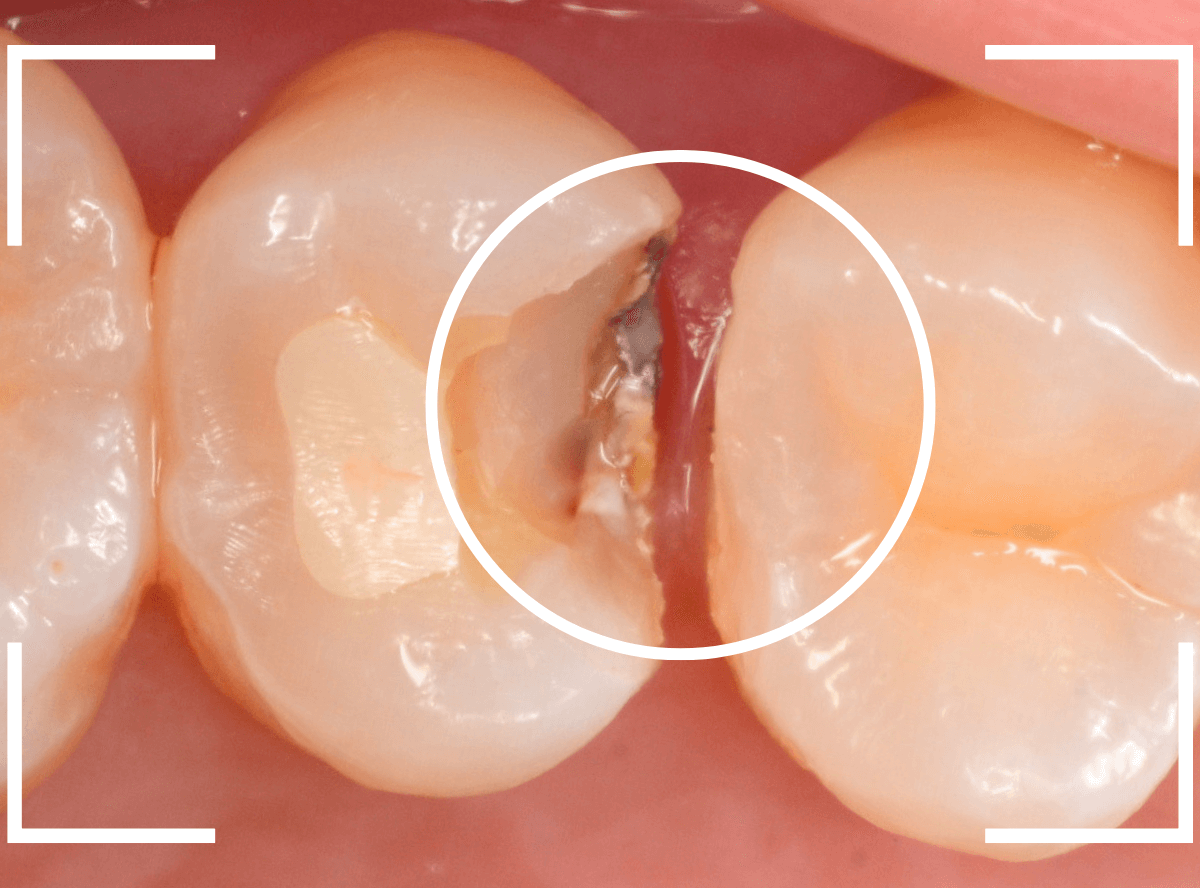

虫歯の治療を開始します。

隣の歯とのすき間を中心に広い虫歯になっていました。

虫歯治療後、特に症状もなく経過観察できましたので、つめものを作る治療に入ります。